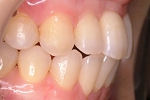

CASE3

前歯1本だけが出ています、矯正で治りますか?

(23歳/女性)↓

||||||||

概要・担当医コメント:

前歯の唇側傾斜/マルチブラケット装置/非抜歯

動的治療期間15ヶ月(15回)/費用概算:60万円.

歯列アーチの形態修正に必要なスペースを微量のエナメル質の研磨により創生し,当初の計画通りに歯を移動させました.